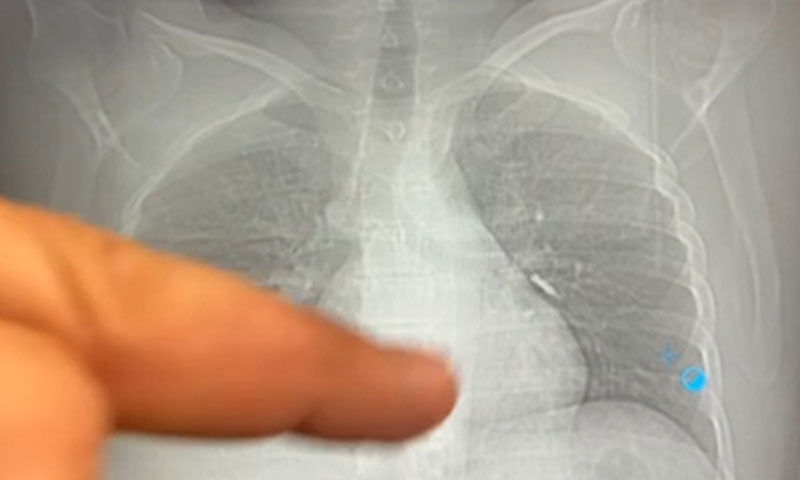

Daha sonra hasta için yeniden bronkoskopi planladıklarını ancak bu süreçte hasta şiddetli bir öksürük geçirdiğini anlatan Aksoy, "Şiddetli öksürük sonrası yapılan kontrol akciğer filminde implant vidası görünmedi. Bunun üzerine toraks ve batın BT (bilgisayarlı tomografi) görüntülemesi istedik. Sonuçlarda implantın akciğerden çıktığı ve vücutta herhangi bir yerde bulunmadığı tespit edildi" diye konuştu.